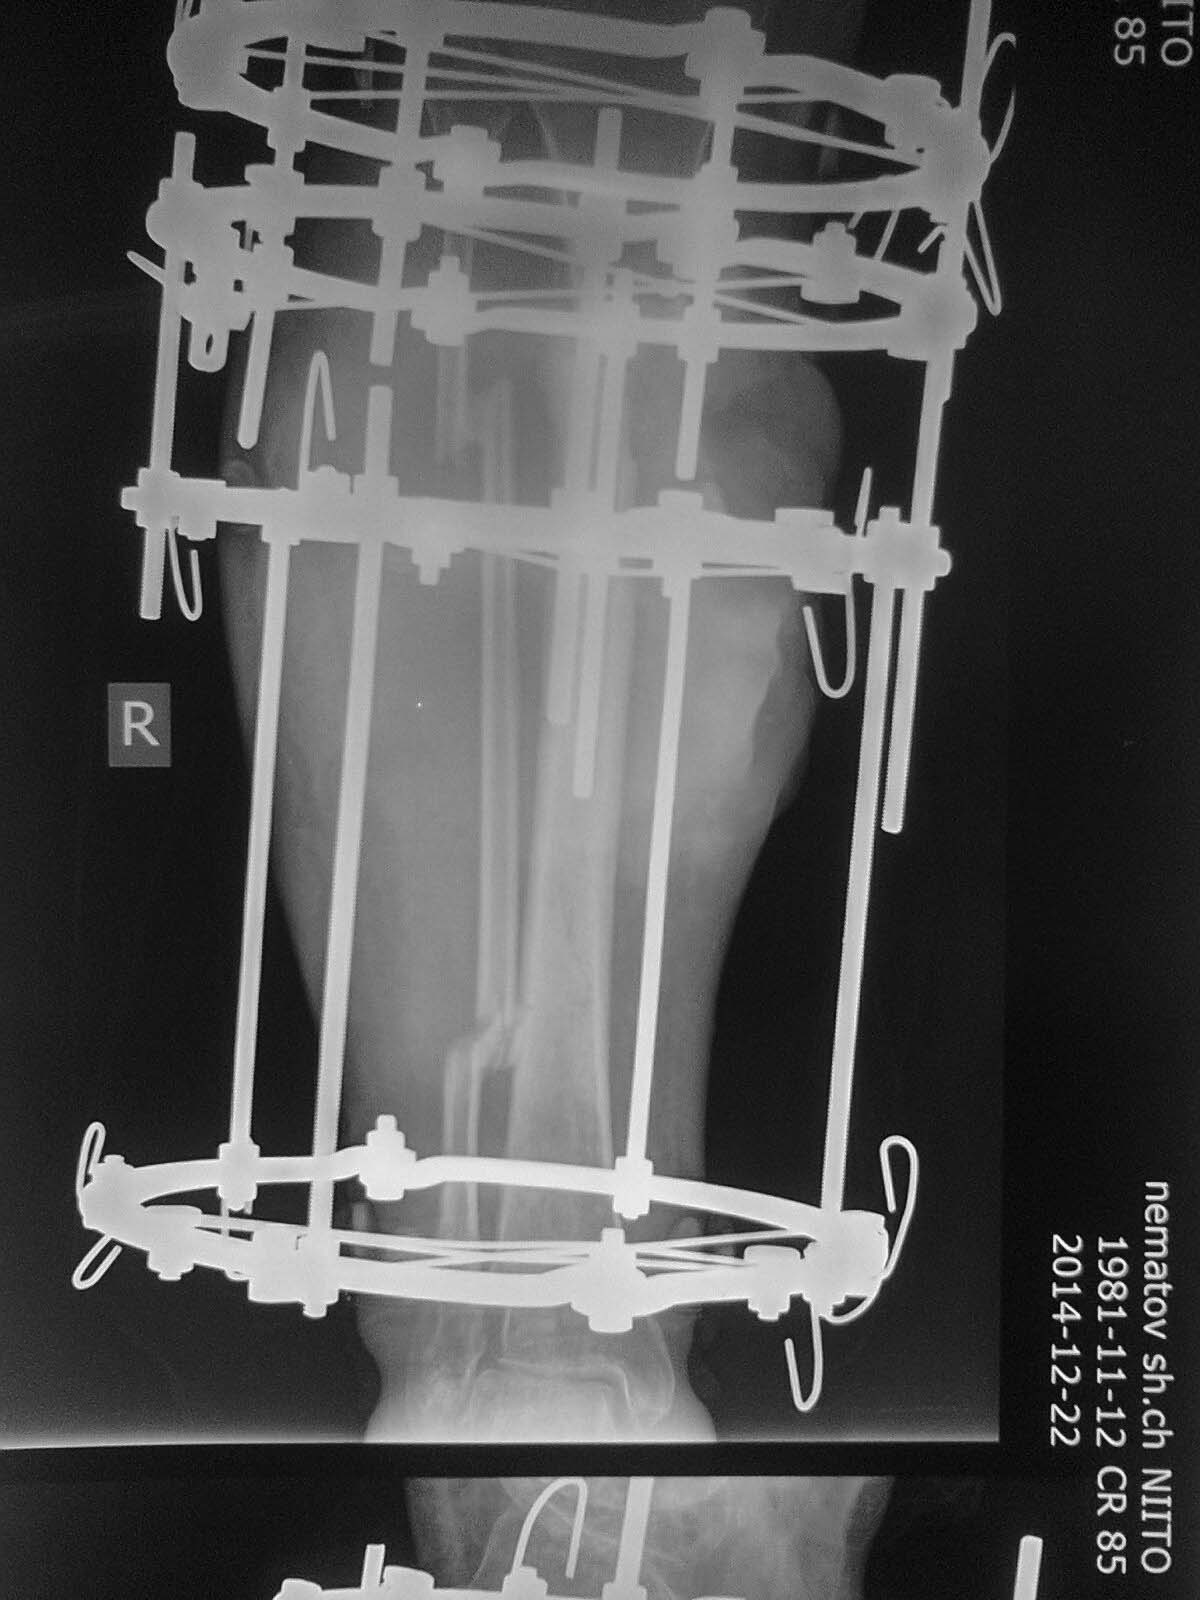

Доброго времени суток, уважаемые коллеги!Прошу Вашей помощи в лечении пациента Н. Пациент, 33 г. Травма в мае 2014 года в результате ДТП (сбит машиной). Оперирован в институте (или центре) травматологии и ортопедии одной из среднеазиатских республик (уроженец этой республики). Обратился к нам в августе, по поводу наличия гнойной раны внутренней поверхности голени с обильным отделяемым. (Рентгенограммы- фото 1). Выполнено: остенекрсеквестрэктомия, резекция концов отломков, перемонтаж аппарата (фото 2). Рана успешно зажила, пациент исчез из вида. Неделю назад пришел снимать аппарат с рентгенограммами (фото 3,4). Ходит с полной безболезненной нагрузкой на конечность, АВФ стабилен, раны от опорных элементов спокойны, отек конечности умеренный, в проекции бывшей гнойной раны- втянутый рубец (если необходим внешний вид конечности, то смогу выложить на следующей неделе,наверное). Учитывая большой дефект кости по задней поверхности кости, боимся, что при нагрузке без аппарата произойдет перелом. Вопрос: что делать? Наши варианты: 1.снять АВФ, рассверлить канал, установить штифт с антибактериальной мантией в виде "протеза" кости; 2.Резекция дефектного участка, остеотомия в н/3, перемонтаж АВФ и билокальное замещение дефекта. Что Вы посоветуете? Спасибо всем откликнувшимся.